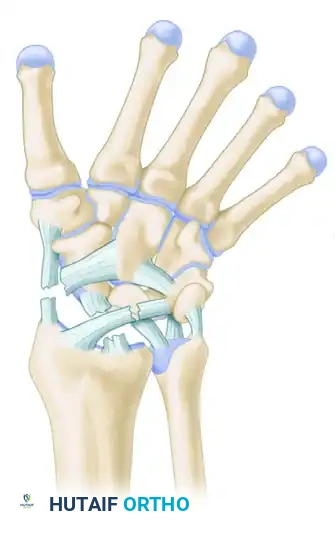

The human wrist is an intricate biomechanical marvel, comprising eight carpal bones, multiple articulating surfaces, and a complex network of intrinsic and extrinsic ligaments. The diagnosis of wrist conditions—whether acute traumatic injuries or chronic degenerative pathologies—demands a meticulous, systematic approach. For the orthopaedic surgeon, mastering the diagnostic algorithm is paramount to preventing long-term sequelae such as carpal collapse, chronic instability, and post-traumatic osteoarthritis (e.g., Scapholunate Advanced Collapse [SLAC] or Scaphoid Nonunion Advanced Collapse [SNAC]).

To accurately diagnose wrist instability, the surgeon must possess a profound understanding of carpal kinematics. Two primary biomechanical models dominate contemporary orthopaedic thought: Taleisnik’s Columnar Concept and Lichtman’s Ring Concept.

Taleisnik proposed that the wrist functions via three distinct longitudinal columns:

* The Central (Flexion-Extension) Column: Comprises the entire distal carpal row (trapezium, trapezoid, capitate, hamate) and the lunate. This column is primarily responsible for the transmission of flexion and extension forces.

* The Lateral (Mobile) Column: Consists solely of the scaphoid, which bridges the proximal and distal rows, providing critical stability and mobility.

* The Medial (Rotary) Column: Comprises the triquetrum, functioning as a pivot point for carpal rotation.

Lichtman expanded upon carpal kinematics by describing the carpus as an oval ring. In this model, the proximal and distal carpal rows act as semirigid posts stabilized by robust interosseous ligaments.

* Normal, controlled mobility occurs primarily at the scaphotrapezial and triquetrohamate joints.

* Pathomechanics: Any break in this ring—whether osseous (e.g., scaphoid fracture) or ligamentous (e.g., scapholunate dissociation)—destabilizes the kinematic chain.